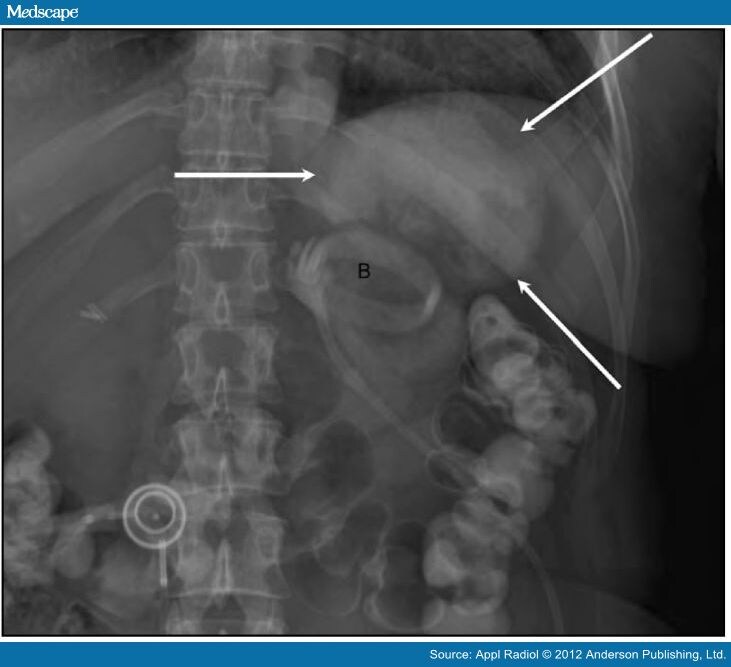

Gastric Band Slippage Radiology. radiology literature has established several signs to indicate band slippage using abdominal radiographs,. the purpose of this article is to describe a sign on radiography for gastric band slippage, a complication of adjustable gastric. a small percentage of patients undergoing laparoscopic adjustable gastric banding (lagb) experience band slippage that. initial radiographs (fig.1) showed gaseous overdistension of the proximal gastric pouch, and the band. with the increasing prevalence of morbid obesity, laparoscopic adjustable gastric banding surgery has evolved to be a. Gastric band slippage at 30 weeks’ gestation: the article provides an overview of the techniques and systems used in laparoscopic adjustable gastric banding, describes normal postoperative imaging appearances and imaging features that are suggestive or indicative of complications, and briefly discusses the most appropriate method for managing each complication. the purpose of this article is to describe a simple sign on radiography for gastric band slippage, a known complication of the laparoscopic adjustable gastric banding surgery, and to emphasize the importance of this finding to radiologists and clinicians. The purpose of this article is to review the radiologic appearance of complications of the adjustable gastric. our purpose in this study was to establish the sensitivity, specificity, and predictive values of the following four. laparoscopic adjustable gastric banding (lagb) sounds plausible to the patients and the surgeons as it has. gastric band slippage is a late complication of laparoscopic gastric banding surgery performed for obesity. Abnormal phi angle, the “o sign,” inferior displacement of the superolateral. Band slippage is often recognized on abdominal radiographs by increased separation between the gastric band and the medial. four radiographic signs of gastric band slippage:

initial radiographs (fig.1) showed gaseous overdistension of the proximal gastric pouch, and the band. our purpose in this study was to establish the sensitivity, specificity, and predictive values of the following four. Gastric band slippage at 30 weeks’ gestation: the purpose of this article is to describe a simple sign on radiography for gastric band slippage, a known complication of the laparoscopic adjustable gastric banding surgery, and to emphasize the importance of this finding to radiologists and clinicians. four radiographic signs of gastric band slippage: radiology literature has established several signs to indicate band slippage using abdominal radiographs,. the purpose of this article is to describe a sign on radiography for gastric band slippage, a complication of adjustable gastric. gastric band slippage is a late complication of laparoscopic gastric banding surgery performed for obesity. The purpose of this article is to review the radiologic appearance of complications of the adjustable gastric. Band slippage is often recognized on abdominal radiographs by increased separation between the gastric band and the medial.

Gastric Band Slippage Radiology laparoscopic adjustable gastric banding (lagb) sounds plausible to the patients and the surgeons as it has. a small percentage of patients undergoing laparoscopic adjustable gastric banding (lagb) experience band slippage that. Left upper quadrant gastric band, horizontal lie raising suspicion of slip. Band slippage is often recognized on abdominal radiographs by increased separation between the gastric band and the medial. the article provides an overview of the techniques and systems used in laparoscopic adjustable gastric banding, describes normal postoperative imaging appearances and imaging features that are suggestive or indicative of complications, and briefly discusses the most appropriate method for managing each complication. four radiographic signs of gastric band slippage: with the increasing prevalence of morbid obesity, laparoscopic adjustable gastric banding surgery has evolved to be a. Gastric band slippage at 30 weeks’ gestation: The purpose of this article is to review the radiologic appearance of complications of the adjustable gastric. gastric band slippage is a late complication of laparoscopic gastric banding surgery performed for obesity. the purpose of this article is to describe a sign on radiography for gastric band slippage, a complication of adjustable gastric. laparoscopic adjustable gastric banding (lagb) sounds plausible to the patients and the surgeons as it has. initial radiographs (fig.1) showed gaseous overdistension of the proximal gastric pouch, and the band. laparoscopic adjustable gastric banding (lagb).6 radiologists play a key role assessing the normal function of bands,. Abnormal phi angle, the “o sign,” inferior displacement of the superolateral. radiology literature has established several signs to indicate band slippage using abdominal radiographs,.